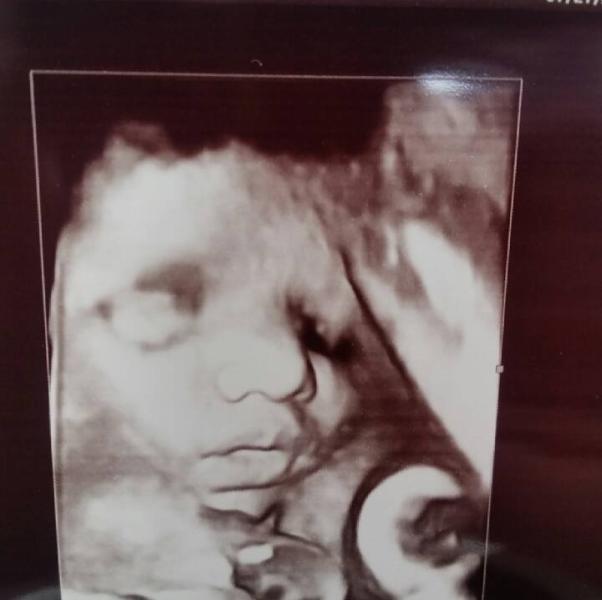

He is perfect, the doctor even said so. Official medical opinion. :)